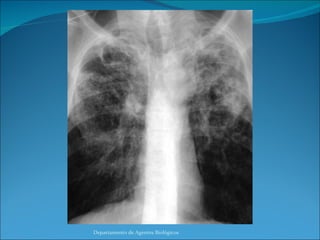

La Infección es lograda cuando el bacilo alcanza el alveolo pulmonar y posteriormente es fagocitada por los macrófagos del polvo, donde se replica intracelularmente.  El equilibrio entre la actividad bactericida del macrófago y la virulencia del bacilo es la que determina la efectividad de la fagocitosis. Formación de un granuloma produciendo lesión histica. Células multinucleadas de Langanhs – Necrosis Caseosa Diseminación – Fibrosis y Calcificación de lesiones pulmonares. Departamento de Agentes Biológicos

La Infección eslograda cuando el bacilo alcanza el alveolo pulmonar y posteriormente es fagocitada por los macrófagos del polvo, donde se replica intracelularmente. El equilibrio entre la actividad bactericida del macrófago y la virulencia del bacilo es la que determina la efectividad de la fagocitosis. Formación de un granuloma produciendo lesión histica. Células multinucleadas de Langanhs – Necrosis Caseosa Diseminación – Fibrosis y Calcificación de lesiones pulmonares. Departamento de Agentes Biológicos